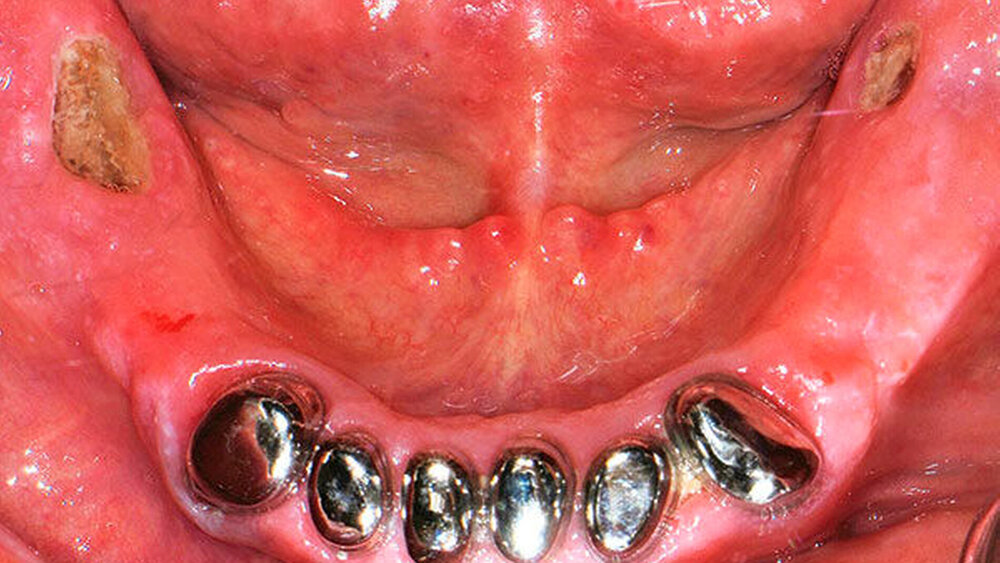

Stand heute ist aber die gründliche intraorale Inspektion noch immer der Goldstandard zur frühzeitigen Identifikation der Nekrose. Das Leitsymptom einer Medikamenten-assoziierten Kiefernekrose ist demnach der inspektorisch oder sondenpalpatorisch freiliegende Knochen [Grötz, 2012; Ruggiero, 2014]. Hierbei ist anzumerken, dass im frühen Stadium intraorale Fisteln vorliegen können, was – in Anbetracht der oben genannten Diskussion – dem inspektorisch freiliegenden Knochen gleichzusetzen ist [Grötz, 2016]. Weitere häufige Symptome sind Mundgeruch, Weichgewebsschwellungen, intra- oder extraorale Fisteln sowie Abszedierungen. Möglich sind auch eine Schädigung der Nervenfunktion (vor allem des Nervus alveolaris inferior), eine Sinusitis [Voss, 2016] sowie pathologische Frakturen des Unterkiefers [Otto, 2009]. Zusätzlich treten in vielen Fällen ausgeprägte Schmerzen auf. Diese sind jedoch kein direktes Symptom, sondern vielmehr die Konsequenz einer stattfindenden (Super-) Infektion der Nekrose [Grötz, 2016].

Das inspektable Erscheinungsbild variiert stark von kleinen sondierbaren Fistelungen bis zu großflächigen Mundschleimhautdefekten. Bei bereits freiliegendem Knochen, stellt sich dieser meist als gelblich, gräulich bis hin zu grünlich verfärbt (mit vergrößerter Porosität) und häufig aufgeweichter Struktur dar. Möglich sind ebenfalls eitriger Ausfluss (auf der Basis einer Superinfektion) und in manchen Fällen gelockerte Knochenanteile im Sinne eines Knochen-Sequesters.